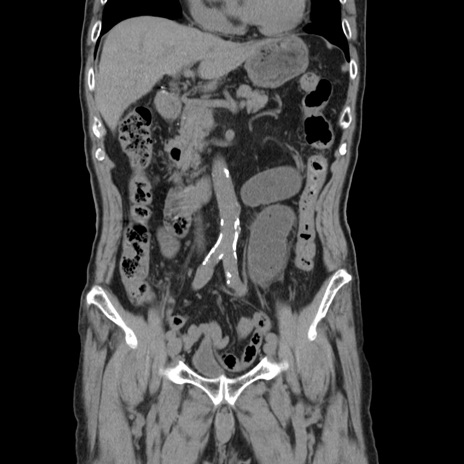

症例24(冠状断像)

【症例】80歳代男性

【主訴】左側腹部痛、嘔吐

【現病歴】本日早朝より左腹部に痛みあり。昼頃嘔吐認めたため、救急要請。

【既往歴】直腸癌(Mile手術)、胆摘

【身体所見】意識清明、BT 35.9℃、BP 221/93mmHg、SpO2 97%(RA) 、腹部:左ストーマ周囲に限局性の腹部膨隆あり。 膨隆部自発痛・圧痛あり・軟。

【データ】WBC 7700、CRP 0.09